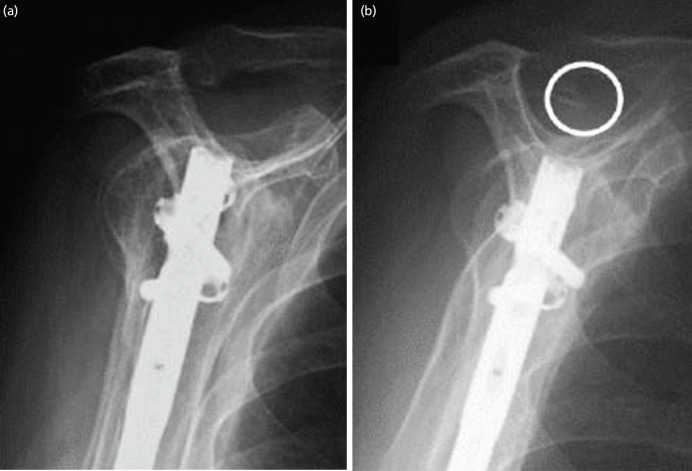

Introduction: Antegrade intramedullary nail fixation for humeral shaft fractures yields satisfactory union rates. However, one of the related concerns is damage to the rotator cuff during nail insertion, which may affect long-term outcomes. The effect of a rotator cuff lesion on mid- and long-term shoulder outcomes remains unknown. This study aimed to investigate the incidence of rotator cuff tears 5 years or more after intramedullary nailing for humeral shaft fractures and to determine the impact of post-operative rotator cuff tears on mid-term outcomes.

Material and methods: We retrospectively identified 27 patients who underwent antegrade intramedullary nail fixation for traumatic humeral shaft fractures and received follow-up for at least 5 years post-operatively. The patients were divided into two groups: those without tears and those with partial or complete tears, diagnosed using ultrasonography. We compared the functional and radiological shoulder outcomes between the two groups.

Results: Of the 27 patients, 10 had partial or complete supraspinatus tears with a mean follow-up of 7.5 years postoperatively. The incidence of acromial spurs was significantly higher in patients with partial or complete tears than in those without tears (P<0.001). There were no significant differences in the age and sex-adjusted Constant score, or the American Shoulder and Elbow Surgeon score between the two groups.

Conclusion: Our results revealed that 37% of patients developed partial or complete supraspinatus tendon tears in the mid-term. Post-operative rotator cuff tears were significantly associated with the formation of acromial spurs; however, they had no significant effect on mid-term shoulder functional outcomes.